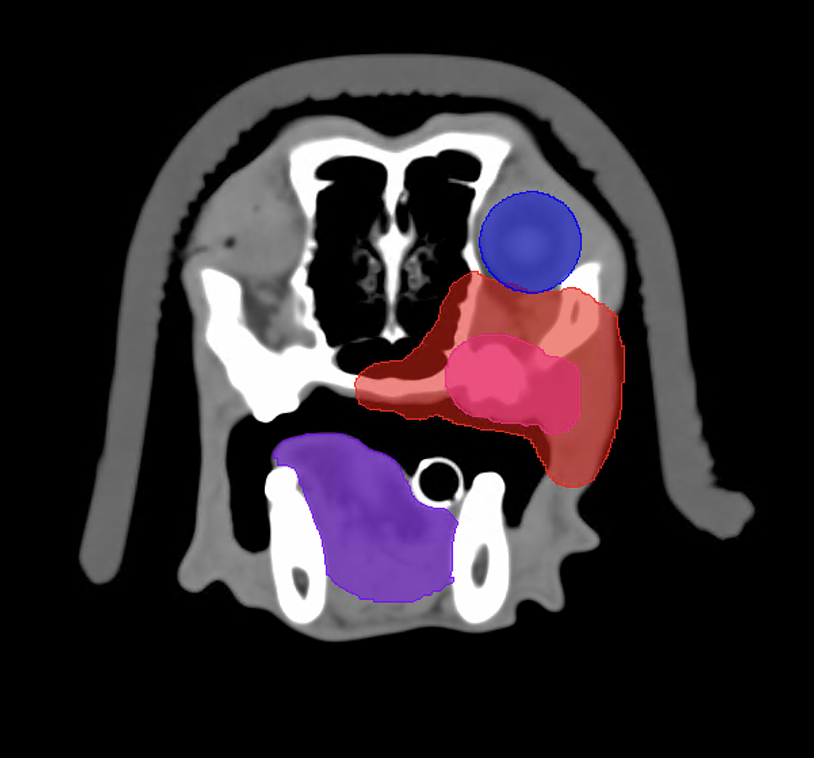

Die Strahlentherapie sowie die jeweils notwendigen Narkosen sind gut verträglich und sicher, sodass Komplikationen extrem selten sind. Im Verlauf der Strahlentherapie ist aber mit Reaktionen zu rechnen, die bereits im Vorfeld aufgeklärt und besprochen werden müssen. Grundsätzlich sind frühe von späten Strahlenreaktionen zu unterscheiden. Frühe Strahlenreaktionen sind bei definitiven Protokollen ausgeprägter als bei palliativen, treten ca. 14 Tage nach Therapiebeginn auf, heilen aber auch bis ca. 21 Tage nach Therapieende vollständig ab. Der vorliegende Fall zeigt eine Vielzahl von zu erwartenden Strahlenreaktionen sehr eindrücklich. In Abbildung 1 ist ein Schnitt des CT zur Strahlentherapieplanung auf Höhe M1 dargestellt. Neben dem Tumorvolumen ist auch das Planungsvolumen (späterer Hochdosisbereich) sowie die Risikoorgane Auge und Zunge konturiert. Aus dieser Abbildung sind die zu erwartenden Nebenwirkungen gut abzuschätzen, da folgende Strukturen im Hochdosisbereich liegen: Maulschleimhaut, Teile der Nasenhöhle, kutane Haut. Außerdem reicht das Planungsvolumen bis an das Auge heran, sodass auch dieses einem Risiko ausgesetzt ist.